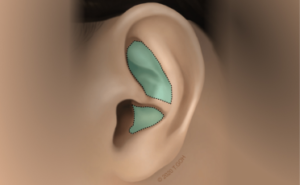

Choosing to combine the intricate skills of microsurgery with aesthetic surgery, Dr Goh specialises in gynaecomastia, surgery of the Asian face, particularly Asian eyelid surgery and rhinoplasty.

Blending the precision of microsurgery with the artistry of aesthetic surgery, Dr Goh has a special interest in gynaecomastia, facial procedures, including ptosis and eyelid surgery, as well as rhinoplasty.